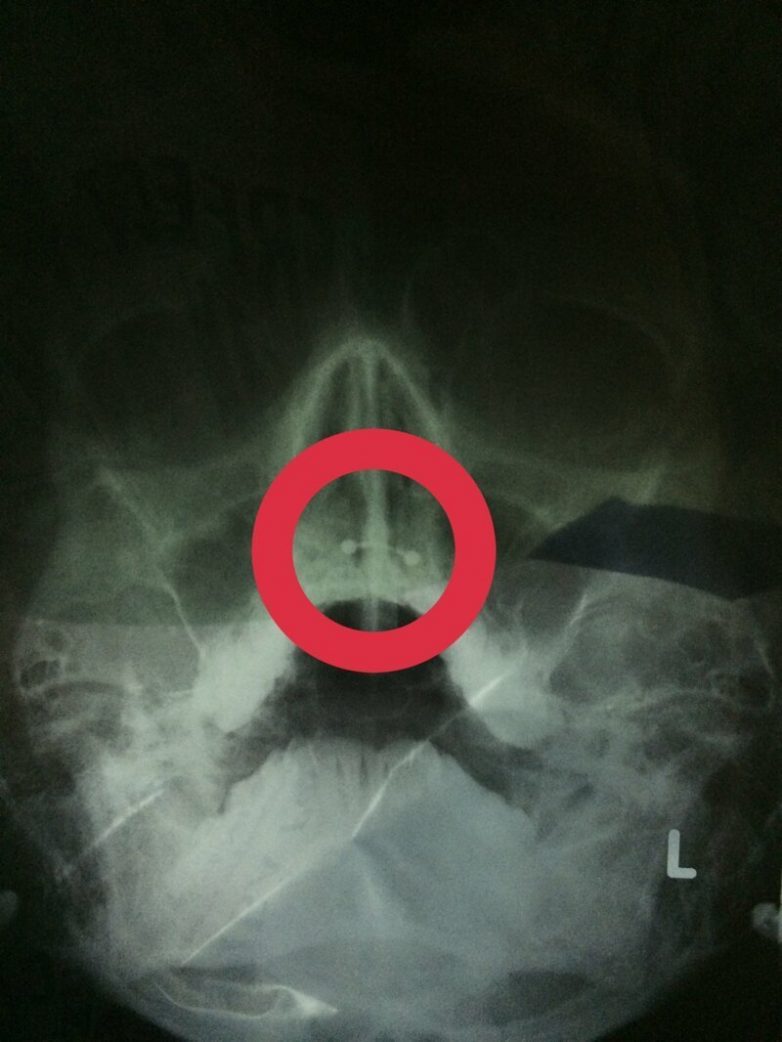

А это снимок человека с гипердонтией (аномалия числа зубов)